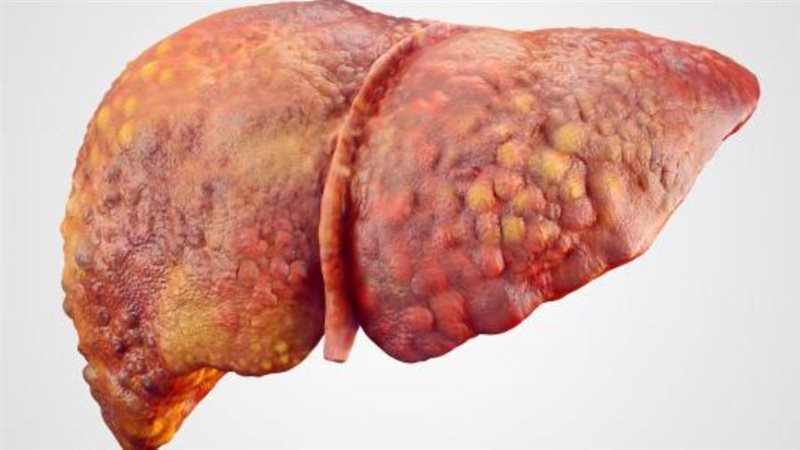

3 أسباب تؤدي إلى الإصابة بالتليف الكبدي

أوضحت وزارة الصحة والسكان، الأسباب الرئيسية التي تؤدي إلى الإصابة بالتليف الكبدي.

- الإصابة بالفيروسات الكبدية بي وسي.

- الاستخدام المفرط فى الكحول.

- الكبد الدهنى فى بعض الأحوال.